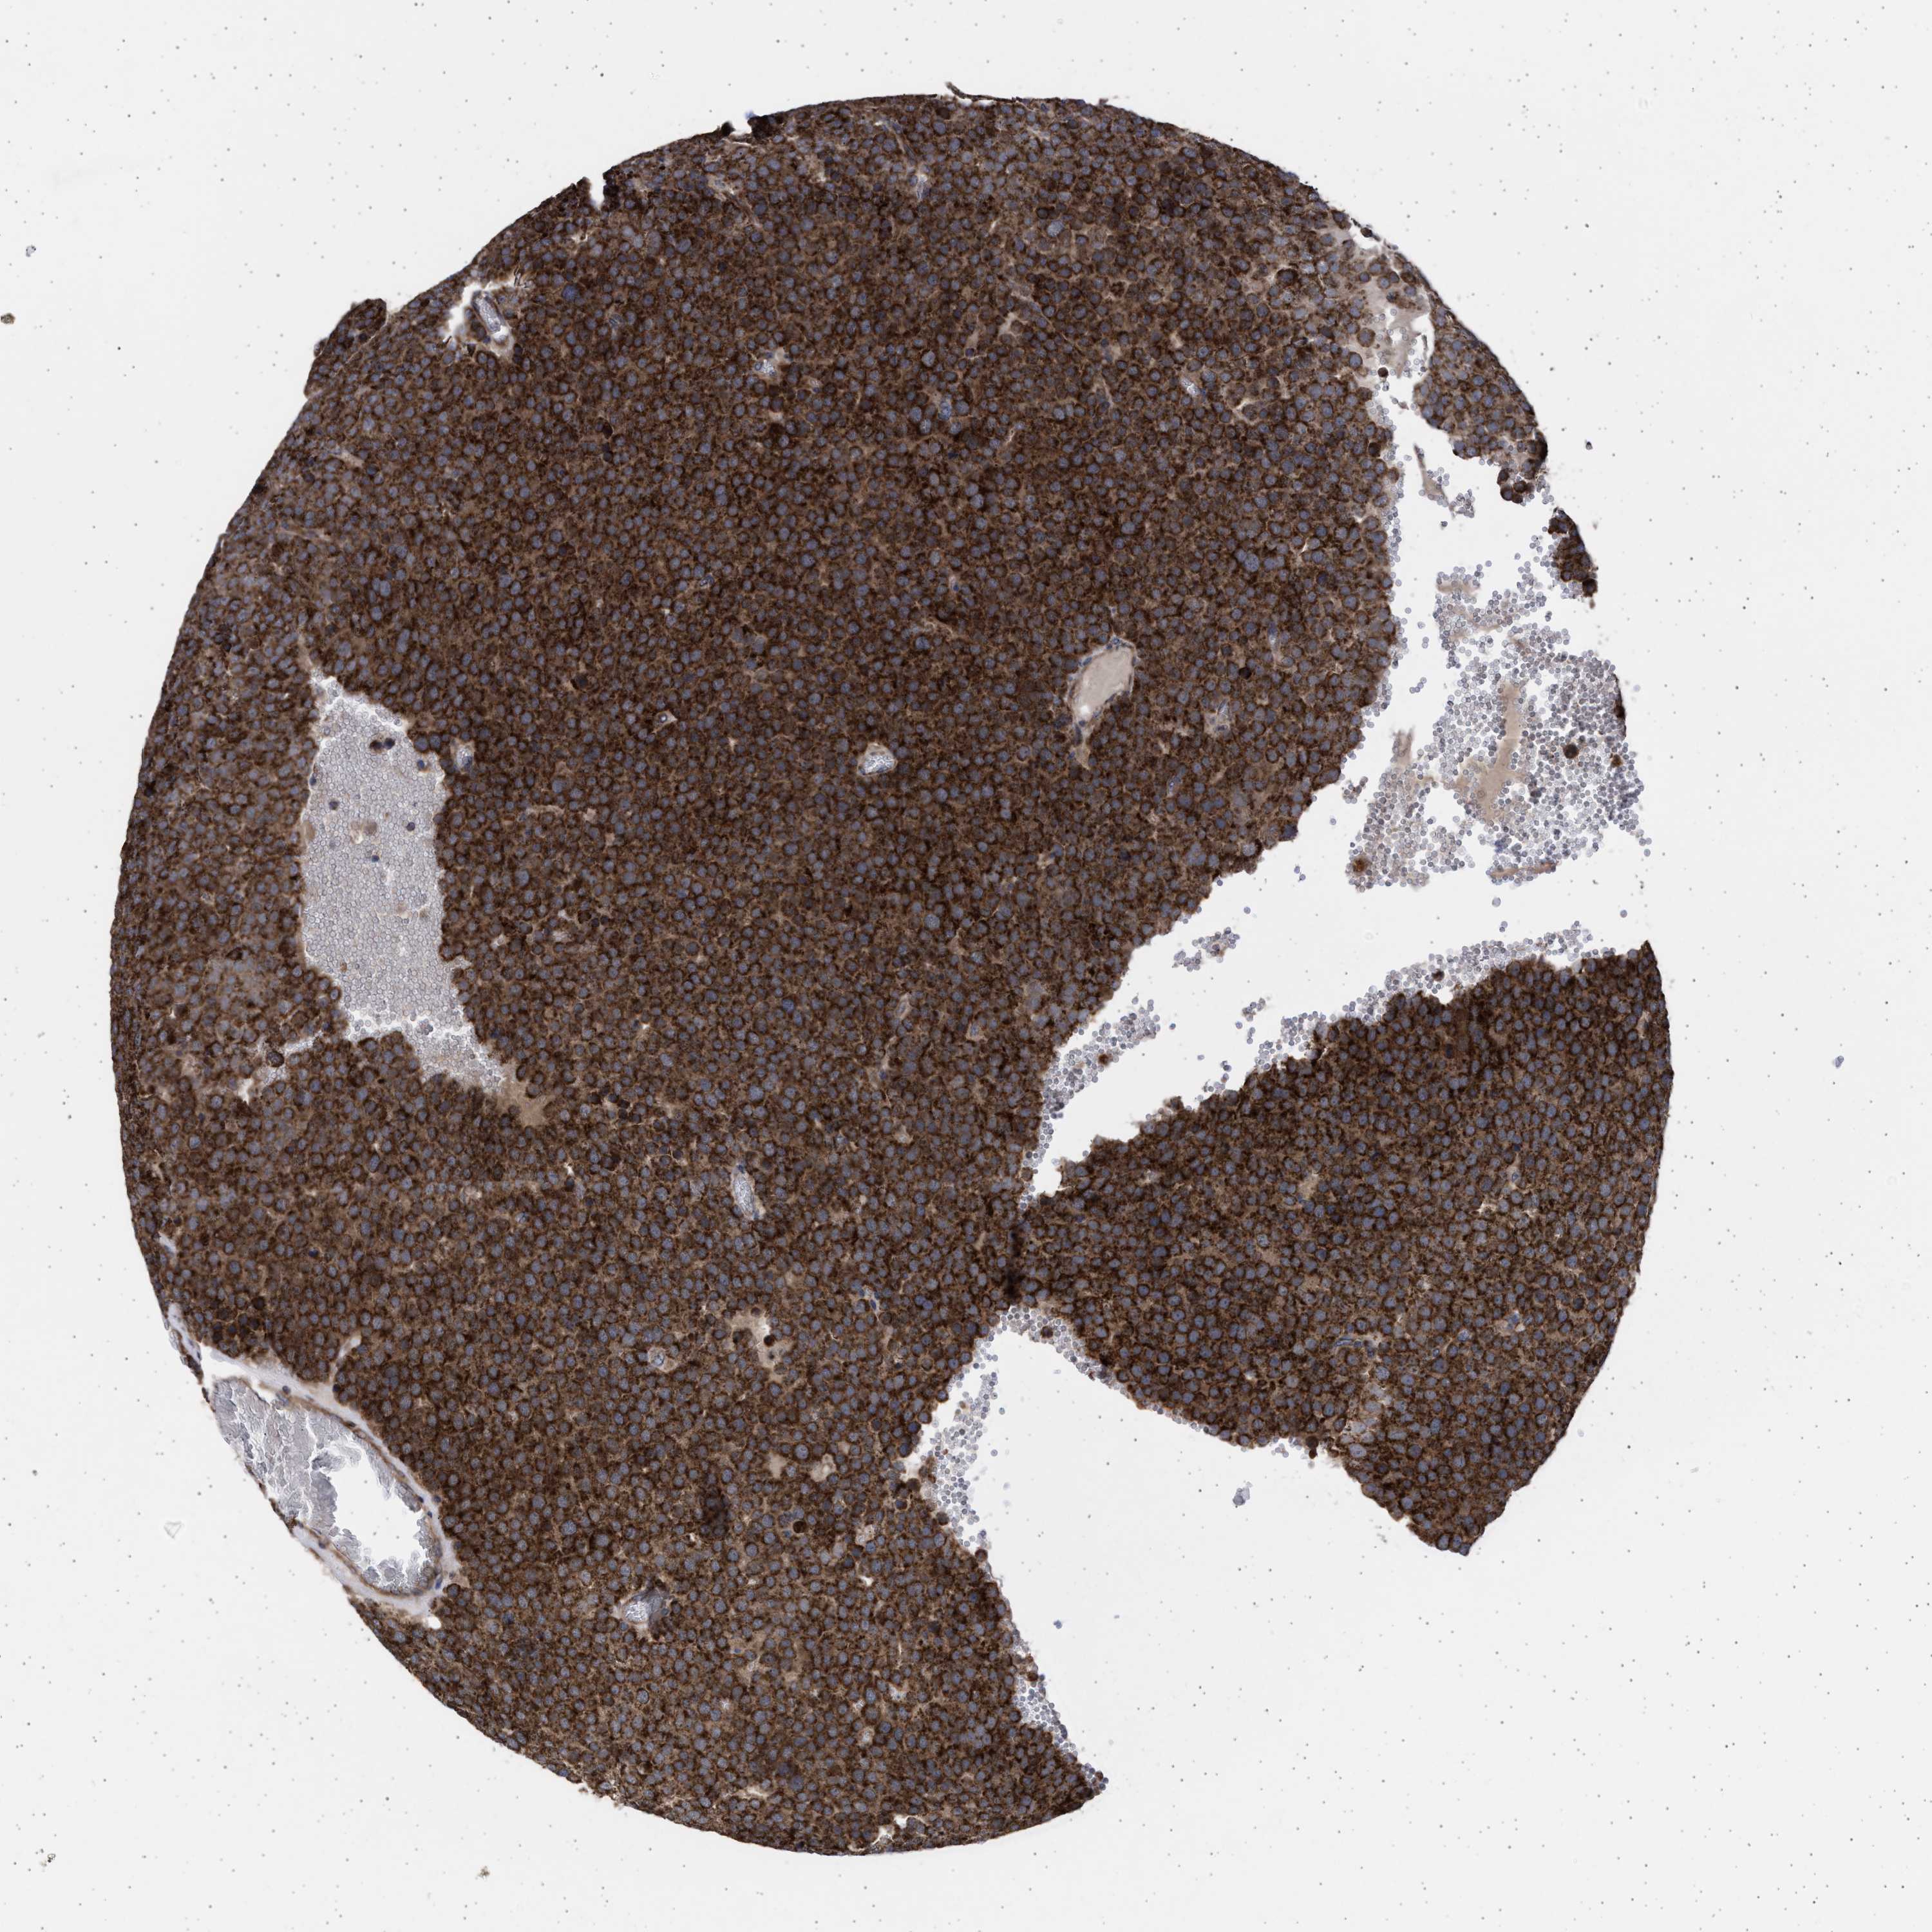

TESTIS CANCER - Protein expressioni

A mouse-over function shows sample information and annotation data. Click on an image to view it in a full screen mode. Samples can be filtered based on level of antibody staining by selecting one or several of the following categories: high, medium, low and not detected. The assay and annotation is described here.

Note that samples used for immunohistochemistry by the Human Protein Atlas do not correspond to samples in the TCGA dataset.

Antibody stainingi

Antibody staining in the annotated cell types in the current human tissue is reported as not detected, low, medium, or high, based on conventional immunohistochemistry profiling in selected tissues. This score is based on the combination of the staining intensity and fraction of stained cells.

Each image is clickable and will lead to virtual microscopy that enables deeper exploration of all samples and also displays staining intensity scores, fraction scores and subcellular localization as well as patient and tissue information for each sample.

Antibody HPA023010

Antibody HPA052380

Staining

High

Medium

Low

Not detected

Intensity

Strong

Moderate

Weak

Negative

Quantity

>75%

75%-25%

<25%

None

Location

Nuclear

Cytoplasmic/membranous

Cytoplasmic/membranous,nuclear

Carcinoma, Embryonal, NOS

Seminoma, NOS

Teratoma, malignant, NOS